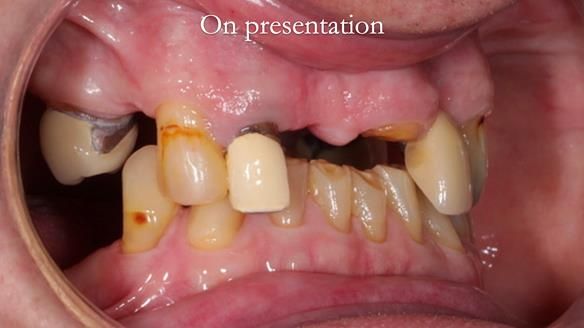

This edition features the case of Edgar, who sought help for a poorly fitting, acrylic-based partial denture that rocked, affected his speech, and caused discomfort. After considering various treatment options, including dental implants, Edgar opted for a metal-based removable partial denture, designed by myself with input from my technician, Rowan Garstang.

Treatment Process: I provided the clinical work while Rowan Garstang delivered the technical aspects. The treatment required fifteen visits to fit and review Edgar.